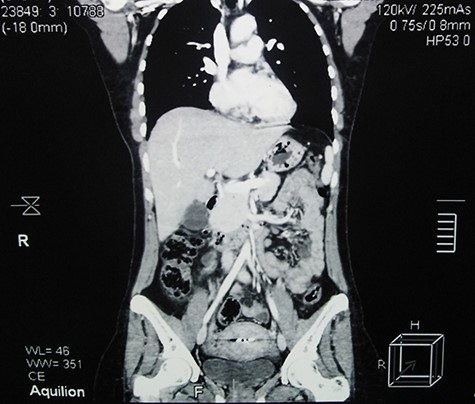

Contrast-enhanced abdominal CT scan 5 months after surgery shows full recovery and no evidence of recurrence.

The post-operation period was uneventful and 5-month follow-up, which consisted of a single CT scan and regular clinical examinations, showed no evidence of recurrence (Fig. 4).

In UCD, surgery is usually curative in which the lesions are removed completely or partially [3]. Furthermore, systemic steroids may provide symptomatic relief, and radiation therapy could be considered. Prognosis in UCD is excellent and patients are usually cured after lymph node excision. Patients may develop lymphoma and/or paraneoplastic pemphigus which could lead to fatal consequences for UCD patients [8]. Regarding this case, removing the mass completely showed acceptable results and 5-month follow-up after surgery showed no evidence of recurrence.